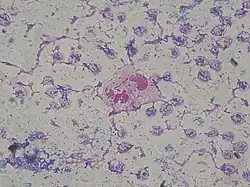

Depending on the nature of infection, an appropriate specimen is collected and sent to a bacteriology laboratory for identification. As with most bacteriological specimens, a Gram stain is performed, which may show Gram-negative rods and/or white blood cells. P. aeruginosa produces colonies with a characteristic "grape-like" or "fresh-tortilla" odor on bacteriological media. In mixed cultures, it can be isolated as clear colonies on MacConkey agar (as it does not ferment lactose) which will test positive for oxidase. Confirmatory tests include production of the blue-green pigment pyocyanin on cetrimide agar and growth at 42 °C. A TSI slant is often used to distinguish nonfermenting Pseudomonas species from enteric pathogens in faecal specimens.

Morphological, physiological, and biochemical characteristics of Pseudomonas aeruginosa are shown in the Table below.